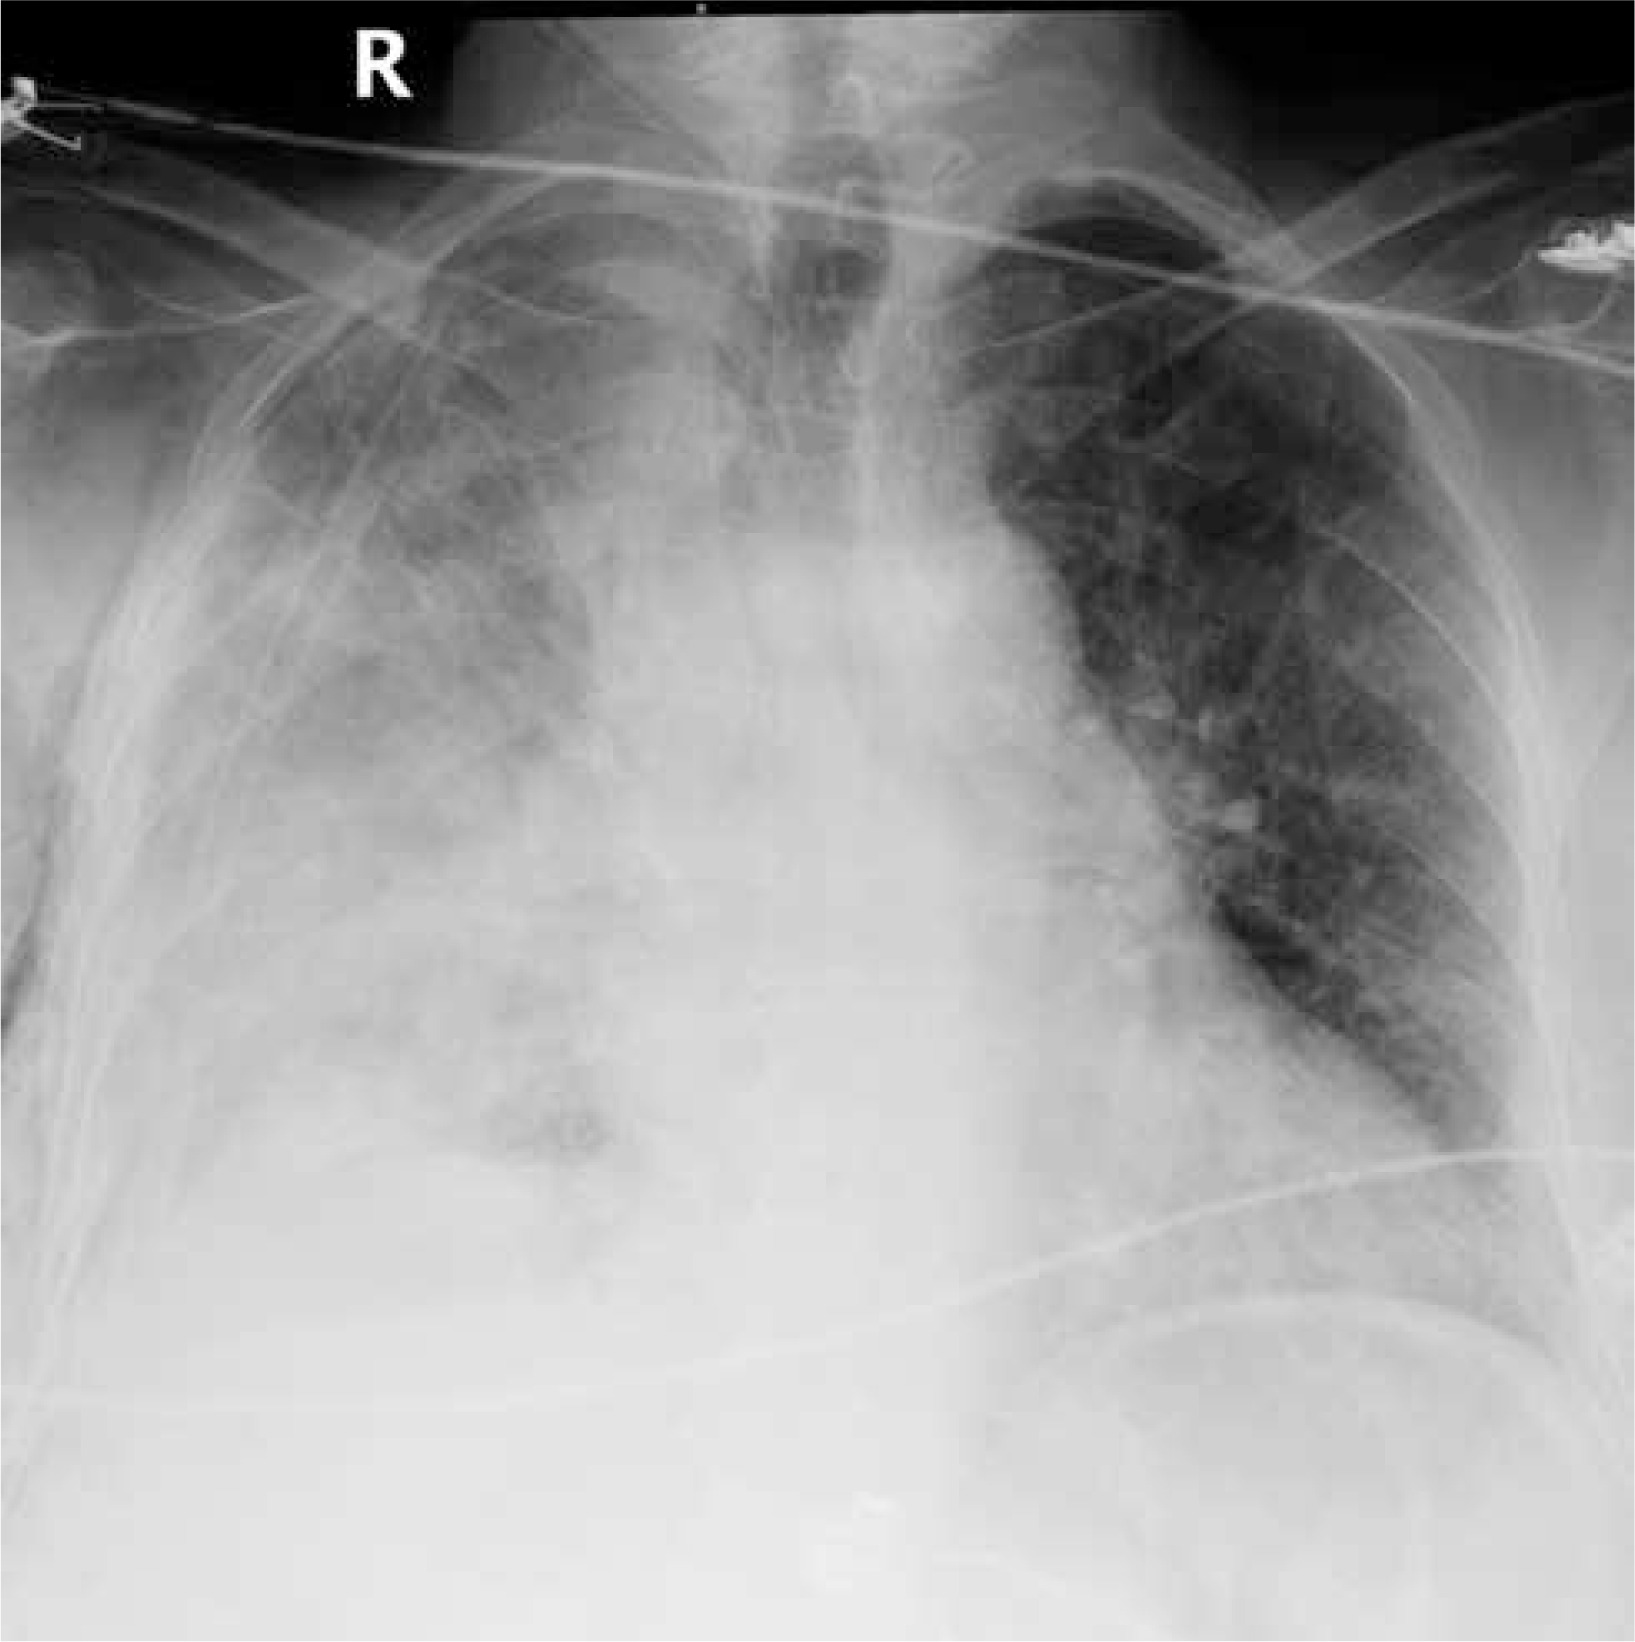

In the thoracic computed tomography of a 63-year-old female patient, a nodule with irregular margins was present in the inferior part of the upper lobe of the right lung. A transthoracic biopsy was taken from the nodule and the pathology result was reported as lung adenocarcinoma. The patient underwent right upper lobectomy and mediastinal lymph node dissection with uniportal VATS. Since the major and minor fissures were incomplete, they were intraoperatively separated with an endoscopic 60-4.8 parenchymal stapler. There was no decrease in hemoglobin value and no pathological finding on chest radiograph until postoperative day 4 (Figure 1). On postoperative day 4, the patient suddenly had hemorrhagic drainage. The patient had 500 ml of hemorrhagic drainage from the chest tube within 30 minutes. The patient was operated on in emergency conditions due to an appearance consistent with hematoma in the right hemithorax on chest radiograph (Figure 2) and decreased hemoglobin level. The uniportal VATS incision was extended posteriorly to provide access to the thorax. After the evacuation of approximately 1000 ml of hematoma, a bleeding focus was noted in the right internal mammary artery and was primarily sutured, and the bleeding was controlled. The bleeding originating from the internal mammary artery was thought to have occurred after the injury by the staple edge placed in the middle lobe to separate the minor fissure. The staple at the end was removed to prevent re-bleeding, and the area was sutured using 4-0 prolene suture. Intraoperatively, the patient received 4 units of erythrocyte suspension replacement. The hemoglobin value postoperatively reached a normal level. The patient’s postoperative chest radiographs showed expanded lungs with no pneumothorax or effusion. The patient with no pathological finding on the chest radiograph taken after the removal of the chest tube was discharged.

Figure 2

Posteroanterior chest radiograph taken on postoperative day 4 when the patient’s drainage started